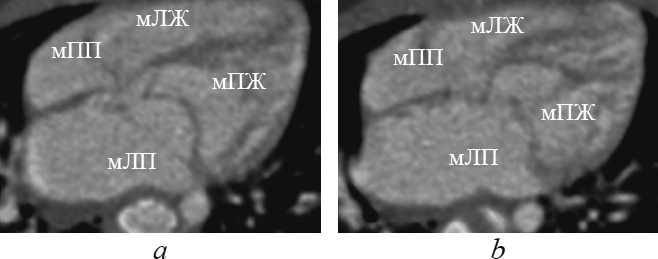

This article contents the results of computed tomography with intravenous bolus contrast media administration data analysis in children with transposition and congenitally corrected transposition of the great arteries with the consequental performing of the multiplanar heart-axis-oriented reformations. Among 148 examined children transposition of great arteries was detected in 13 patients (9 boys and 4 girls aged 1-144 day of life); congenitally corrected transposition was found in 4 cases of children aged from 6 months to 15 years and 6 months (2 boys and 2 girls). In this article comprehensive anatomical criteria of each heart chamber morphology are presented and reformations where these criteria can be seen are shown. Also in the article is given comparative characterization of heart and great arteries structures in transposition and congenitally corrected transposition in every certain heart-axis-oriented reformation. By the results of consequently performed heart-axis-oriented reformations data analysis the peculiar anatomical signs of transposition and congenitally corrected transposition are determined. The results of data analysis show that from the list of offered reformations the peculiar anatomical signs of both kinds of transposition are significantly determined in long-axis of right ventricle inflow tract reformation, left heart chambers reformation, supply ventricle division reformation, short-axis reformation at the level of great arteries. Computed tomographic angiocardiography heart-axis-oriented multiplanar reformations permit full and correct assessment of heart and main vessels, which is important for planning of surgical treatment in congenital heart diseases.